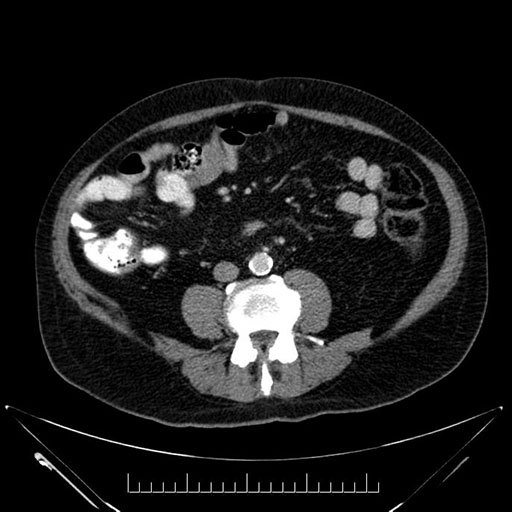

Coronal - stented